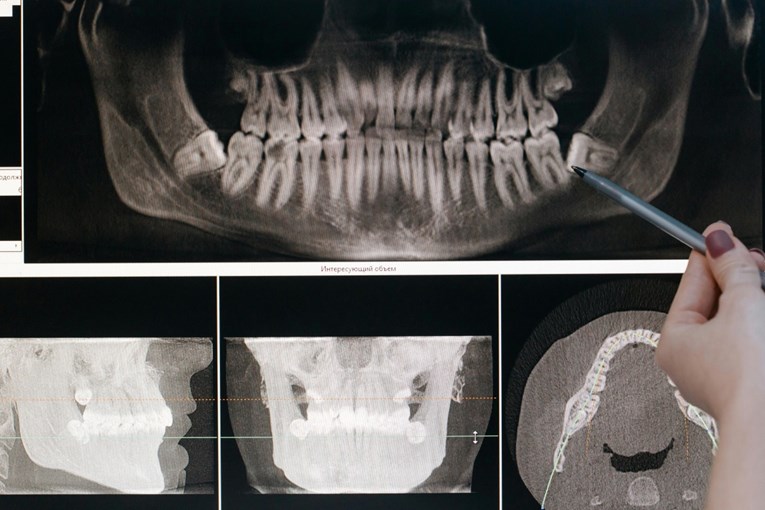

НОВА студија пронајде врска помеѓу стапката со која ги губиме забите во старост и ризикот од смрт. Ова откритие ја истакнува важноста на доброто орално здравје и сугерира дека губењето на забите може да биде клучен индикатор за други сериозни здравствени проблеми, пишува Science Alert .

Иако врската помеѓу губењето на забите и смртноста е позната веќе некое време – генерално, помалку заби значи поголема веројатност за порано умирање – досега немаше податоци за тоа како побрзото губење на забите влијае на оваа поврзаност. За да истражат, тим научници од Универзитетот Сечуан во Кина анализирале податоци за 8.073 постари лица, следејќи ја нивната стапка на губење на забите во однос на смртноста во просечен период од 3,5 години.

Тимот зад студијата сака да ја подигне свеста за важноста на оралното здравје. Редовните посети на стоматолог, миењето на забите двапати на ден и откажувањето од пушење се клучни за одржување на здрави заби. Стоматолошките прегледи овозможуваат следење на бројот на заби и примена на раствори како што се протезите, што би можело да биде сигурен начин за следење на ризикот од болести и смрт кај постарите лица.